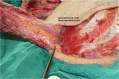

The role of the pectoralis major myocutaneous flap (PMMF) in head and neck reconstruction is challenged recently due to its natural drawbacks and the popularity of free flaps. This study was designed to evaluate the indications and reliability of using a PMMF in the current free flap era based on a single center experience. The PMMF was harvested as a pedicle-skeletonized flap, with its skin paddle caudally and medially to the areola, including the third intercostal perforator, preserving the upper one third of the pectoralis major muscle. The harvested flap was passed via a submuscular tunnel over the clavicle. One hundred eighteen PMMFs were used in 114 patients, of which 76 were high-risk candidates for a free flap; 8 patients underwent total glossectomy, and 30 underwent salvage or emergency reconstruction. Major complications occurred in 4 patients and minor complications developed in 10. Tracheal extubation was possible in all cases, while oral intake was possible in all but 1 case. These techniques used in harvesting a PMMF significantly overcome its natural pitfalls. PMMFs can safely be used in head and neck cancer patients who need salvage reconstruction, who are high risk for free flaps, and who need large volume soft-tissue flaps.